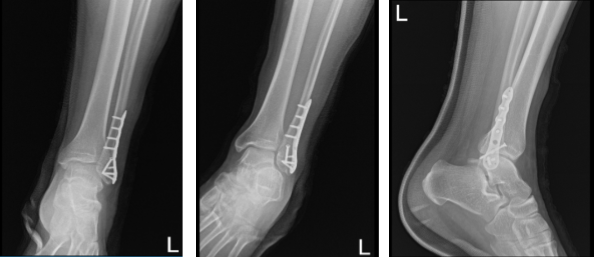

A patient, a 24 year-old male, was seen in the office with pain in his ankle and foot because he fell on ice while returning from work. For aggravating factors, the patient reports standing, walking, lifting, twisting, weight bearing, exercise, and downstairs with associated symptoms of weakness, tingling, swelling, warmth, tender to the touch, and pain with motion. X-ray He was found to have a displaced rotated fracture of the lateral malleolus.

The fracture was found to be externally rotated and collapsed. The fracture was reduced and held with a clamp. Interfragmentary screw was applied from anterior superior to posterior inferior. A 3.5 anterior interfragmentary screw was inserted and the fracture was found to be safely reduced.

A lateral along the fracture and held with an Olive wire. X-ray showed satisfactory reduction in AP and lateral views. The plate was fixed to the distal fibula with the use of four distal locking screws and four proximally nonlocking screws.

After a week from the surgery, the patient was sent for an X-ray. The AP, lateral and oblique. No prior examinations are available for comparison. Examination is performed through an overlying cast partially obscuring bony detail. The patient is status post ORIF distal fibular fracture.

The fracture line is barely visible. The surgical hardware is intact. Visualized aspects of the left talus, calcaneus and tarsal bones demonstrate intact cortical margins with no evidence of an acute fracture. There are no significant degenerative changes. Ankle mortise is well maintained.

There is no appreciable soft tissue swelling. There is no calcaneal plantar spur. It gives the impression that no prior examinations are available for comparison.

Examination is performed through an overlying cast partially obscuring bony detail. The patient is status post ORIF distal fibular fracture. The fracture line is barely visible. The surgical hardware is intact.